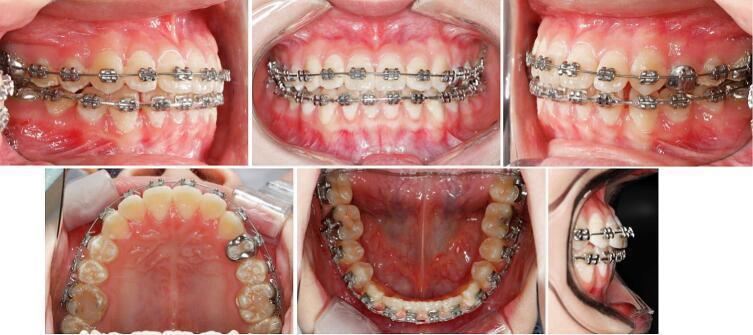

This case report describes the camouflage treatment of a severe skeletal Class III adolescent at the post-pubertal stage.

Protraction facemask combined with a bonded acrylic splint expander was initially used to correct the developing skeletal Class III malocclusion. Then the patient received fixed appliance therapy. The duration of active treatment was 14 months. Anterior crossbite was corrected, along with stable occlusion and harmonious facial condition. The results remain stable at the 5-year follow-up period.